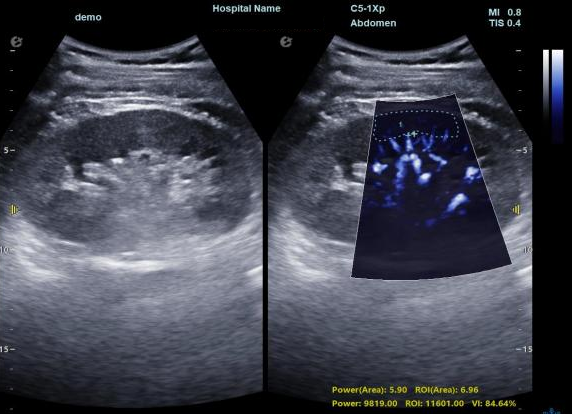

1) 基于OmniSound?平面波超快速平台,超声信号采集帧频提高了200倍(25000Hz)。

2) 可检测20-50μm级细小血管低速血流信号,能看清头发丝1/2粗细的微血管;

3) 通过血管指数(VI)定量评估局部血管密度,以定量化数据实时监测血流灌注情况,预判肾功能恢复情况;

超微视血流显像显示肾脏五级血管

肾脏的灌注评估,RI/VI量化数据

超微视血流显像评估肾移植术后灌注情况